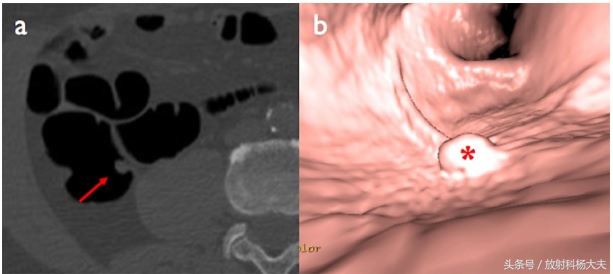

CT上的息肉表现,左图为轴位图像,右图为虚拟内镜技术。可见息肉为突起的小结节。